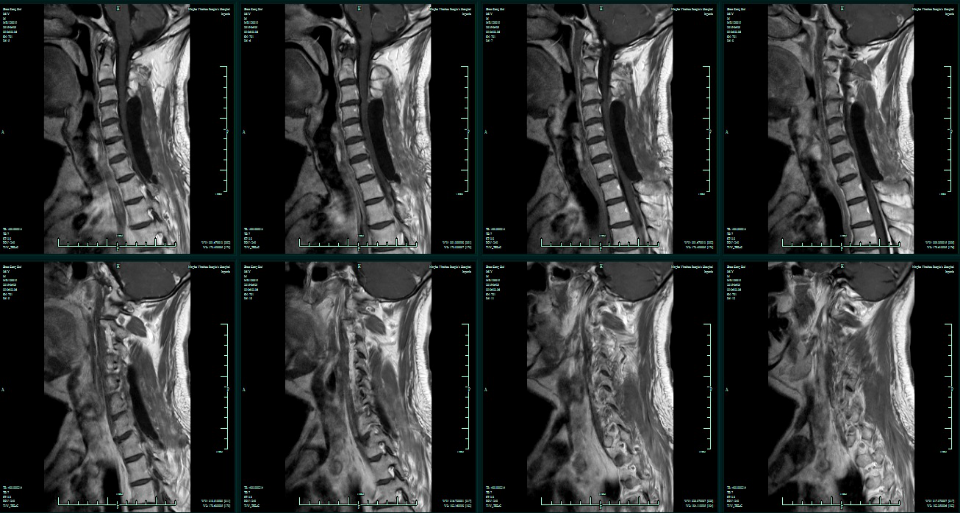

术后3个月,出现双手活动稍不便,行走稍有不稳,查双手肌力左V-级,右IV级。复查MR增强示病灶复发,(手术部位无病灶生长,脊髓腹侧周围可见病灶生长。)

术后3月颈椎MR增强

治疗2周后再次复查MR增强

多次复查颈椎MR增强,提示病灶未再复发。